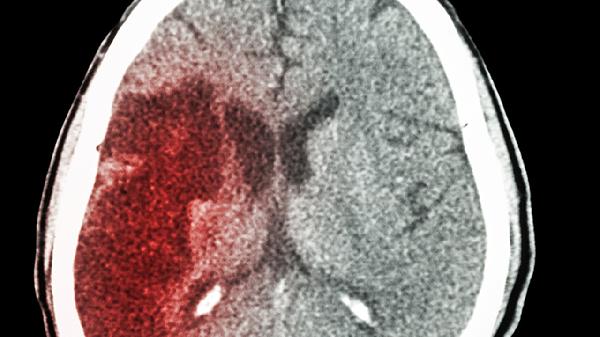

清晨6点,老张像往常一样起床准备晨练,突然感到一阵天旋地转,左半边身体完全不听使唤。家人紧急送医后,医生诊断为急性脑梗。令人意外的是,老张的血压一直控制在正常范围,这让家属百思不得其解。